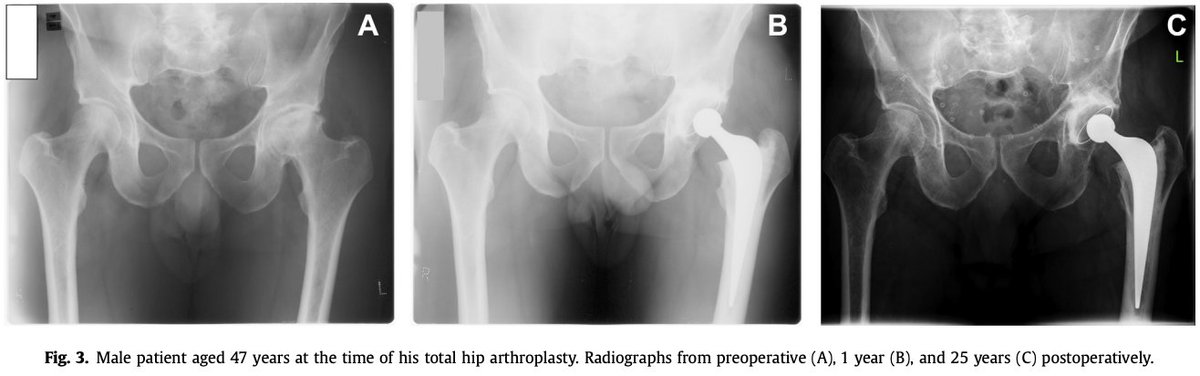

More data showing that #cemented #THAs do very well. Even in the young. @ExeterHipUnit @EdinburghKnee and many others are nodding in agreement https://t.co/pWn7XJ2Yig